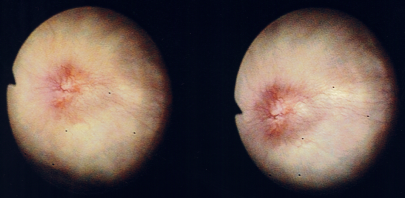

A 70-year-old Caucasian man presented with a three day history of painless gross haematuria associated with storage lower urinary tract symptoms. He is a non-smoker with no family history of bladder cancer. He has a past history of squamous cell carcinoma of the temple, basal cell carcinoma of the eyebrows, plantar fasciitis, rosacea and solar keratosis. Clinical examination was unremarkable. Mid stream urine microscopy and culture confirmed microscopic haematuria and no significant bacterial growth. Urine cytology showed no malignant cells. He had normal PSA, liver function tests, renal function tests, clotting profile and FBC. Ultrasound scan of the kidneys, ureters and bladder showed a 2cm echogenic bladder lesion in the right lateral bladder wall (Figure 1). Cystoscopy showed a 2cm calcified bladder lesion on the posterior wall with another 0.5cm lesion above the trigone (Figure 2). The appearance was highly suspicious of a solid bladder tumor or bladder schistosomiasis. Trans-urethral resection of these two bladder lesions was performed with deep resection. Complete resection was achieved in the smaller lesion but not in the larger lesion due to the density of the calcifications. Bimanual examination under anaesthesia before and after the bladder lesion resection showed no bladder wall thickness or palpable bladder mass. Histology of the resected bladder lesion ruled out bladder malignancy and demonstrated a degenerative eosinophilic material with extensive ossification and accompanying foreign body giant cell reaction in keeping with bladder amyloidosis (Figure 3).

Figure 2 Flexible cystoscopy: 2 cm calcified bladder lesion on the right wall with another 0.5 cm small lesion above the trigon.

Follow-up flexible cystoscopy at 4months under local anaesthesia showed recurrence of the larger, incompletely resected 2cm bladder lesion (Figure 4). Subsequent CT scan with contrast showed a lesion on the right bladder wall. The abdominal organs showed no abnormality and there was no abdominal or pelvic lymphadenopathy (Figure 5). A Pelvic MRI showed an enhancing area of thickening on the right bladder wall with ill-defined peri-vesical fat in that area (Figure 6). The patient had a further cystoscopy and complete resection of the bladder lesion was achieved due to less inclusive calcification. Histology confirmed amyloid deposition, with apple-green birefringence, with extensive ossification and accompanying giant cell reaction and no evidence of malignancy. Immunochemical staining of amyloid deposits, using monospecific antibodies reactive with serum amyloid a protein (SAA), transthyretin (TTR) and Kappa and Lambda immunoglobulin chains was negative. Therefore, the conclusion was that the amyloid is of non-AA type. A further follow up with flexible cystoscopy under local anaesthesia every 6months showed no recurrence of the amyloid lesion in the bladder up to two years after the second resection (Figure 7).

Figure 4 The recurrent lesion had less calcification and had an appearance similar to solid bladder tumor.